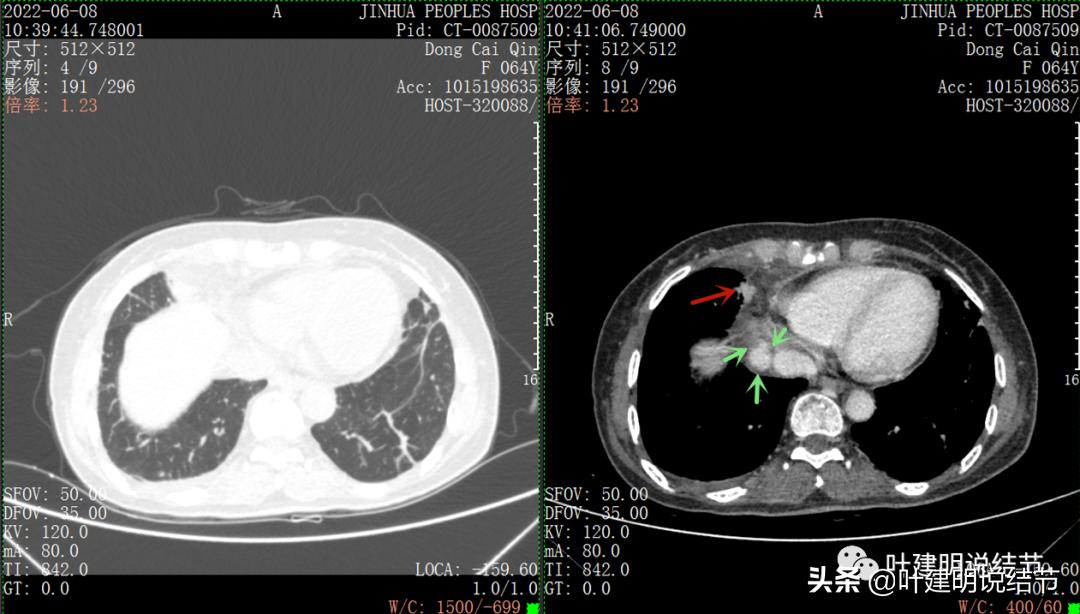

再来看看她的CT增强图像:

以下图片左侧是肺窗,右侧是纵隔窗。红色箭头示病灶,桔色箭头示无名静脉,黄色箭头示支气管,砖色箭头示上腔静脉,蓝色箭头示主动脉,紫色箭头示肺动脉。

病灶占据前纵隔从上到下全程,多中心,密度不均,对心脏与大血管有压迫,没有明显侵犯

病灶表面不平,中间有坏死

上图示最大横断位达5厘米